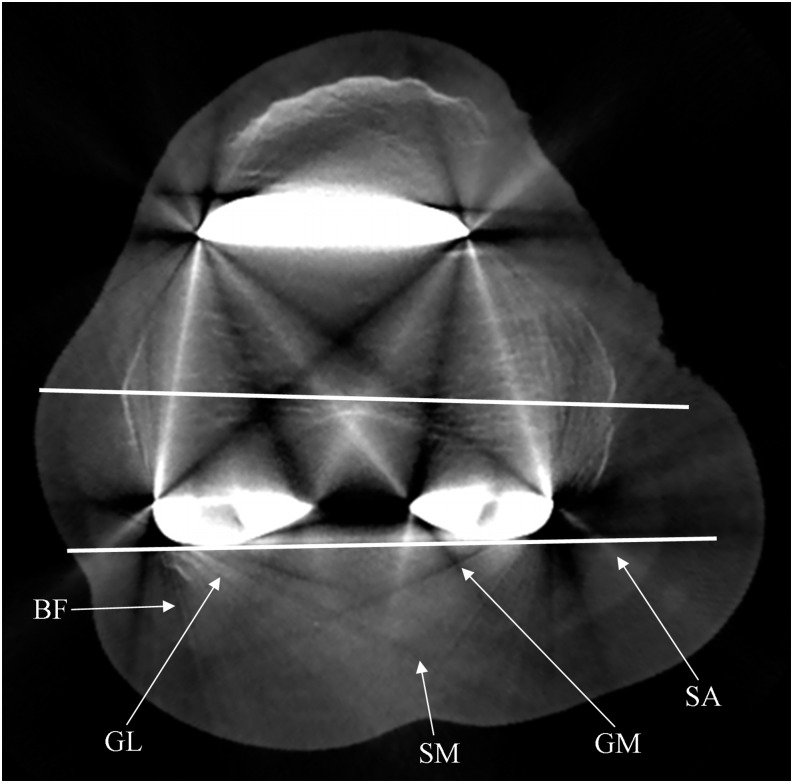

Figure 3.

Cone beam CT axial plane corresponding to the transepicondylar axis, used to measure the femoral component rotational angle. Note the photon starvation artefacts which hamper the detection of the femoral bone. They manifest as obvious alternated hypo-/hyperdense streaks, radiating from the metal prosthesis and opening-up in a fan-like manner. BF, biceps femoris muscle; GL, gastrocnemius lateral muscle; GM, gastrocnemius medial muscle; SA, sartorius muscle; SM, semi-membranosus muscle.

– lower femoral plane, corresponding to the transepicondylar axis. Bone structure was analysed at both femoral flange and posterior femoral condyles, separately (Figures 1 and 3)

– lower femoral plane: biceps femoris, sartorius, semi-membranosus, gastrocnemius medial and gastrocnemius lateral muscles (Figure 3)

In the upper femoral plane, upper tibial plane and lower tibial plane, G2 + G3 was 74.3%, 59.5% and 69.1%, respectively (Table 3), whereas in the lower femoral plane, G0 was predominant. It was 36% and 100% in the evaluation of the anterior and posterior components, respectively; however, analysis of merely femoral bone tissue—thus excluding the patella—was always G0 (100%). Furthermore, all G0 (100%) at 10 and 15 mm were localized in the lower femoral plane.

Biceps femoris, sartorius and semi-membranosus muscles were G3 in 100% in the upper femoral plane, whereas in the lower femoral plane were predominantly G0 (at least 55.1%). Gastrocnemius medial and gastrocnemius lateral muscles were G0 in 100% in the lower femoral plane but were G3 in around 50% and 100% in the upper tibial plane and lower tibial plane, respectively.

Metallic prosthesis affects the X-ray beam in such a way that the criteria for proper image reconstruction via CBCT back projection is not respected.34 Therefore, photon starvation and beam hardening artefacts arise (Figures 3 and 5).

In TKA as in maxillofacial CBCT, anatomical structures located between two or more metallic areas on the same axial plane cannot be evaluated due to major artefacts, such as the detection of the femoral bone in the lower femoral plane case (G0 = 100%) (Figure 3). However, in TKA imaging, deterioration of bone structures measured at every 45° angle around the metallic surface was essentially the same, whereas the artefacts in maxillofacial CBCT show a characteristic location dependent on the position of the metal within the mouth.35 This is probably related to the various differences of morphological, dimensional and structural characteristics between oral and knee prosthesis. In the other three planes where only one metallic area existed (upper femoral plane and tibial planes), bone structure could generally be well or perfectly identified. This proved the efficacy of CBCT in periprosthetic bone study in patients with TKA. Bone structure of the patella can also be always, at least, identified.